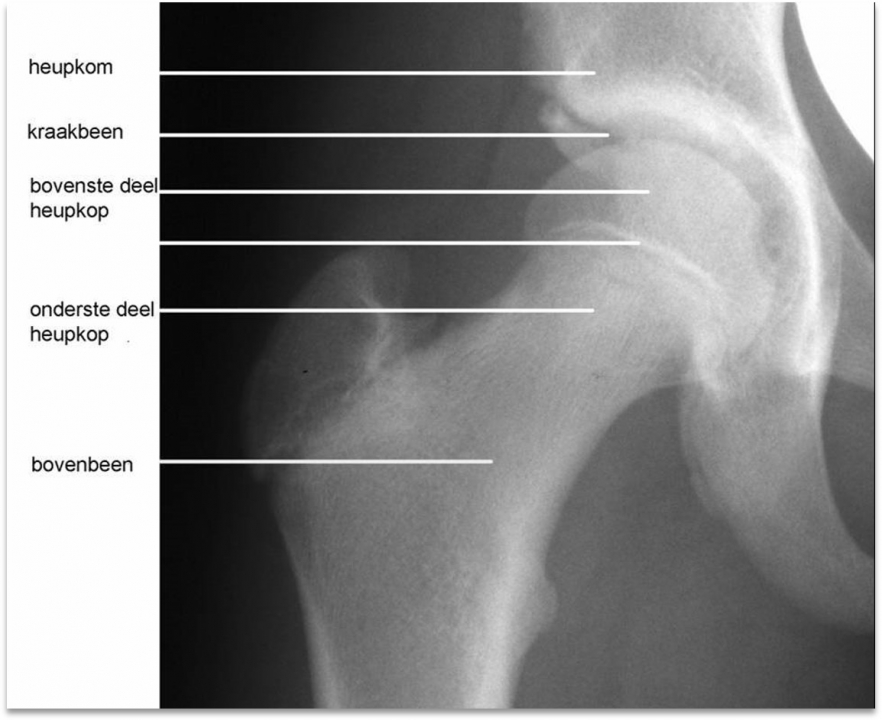

Collumfractuur = Heupfractuur

• De collumfractuur is berucht.

• Het collum is de dunne hals van het dijbeen net onder de heup kop.

• Een collumfractuur heet in de volksmond dan ook gebroken heup. Dit overkomt veel ouderen. Zij vallen, breken hun heup en hebben dan veel pijn.